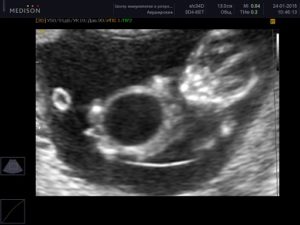

Мегацистисом называют увеличение у плода во время внутриутробного развития мочевого пузыря в продольном размере (больше 8 мм). Кроме этого увеличивается соотношение этого параметра к копчико-теменному размеру (составляет больше 10,4%, при норме — 5,4%). Мегацистис чаще всего обнаруживают на ранних терминах беременности (10-15 неделя) в 0,06-0,19% случаев.

На ультразвуковом исследовании мочевик визуализируется в виде грушевидного или округлого образования. Орган имеет тонкие стенки, расположен в нижней области туловища и увеличивается в размерах в течение беременности матери.

На ранних терминах (11-13 недель) расширенные верхние мочевые пути не всегда свидетельствуют о синдроме мегацистиса и наиболее четко визуализируются только после 14 недели.

Кроме того, увеличенный мочевой пузырь встречается у детей во время внутриутробного развития. Как правило, диагноз мегацистис ставят на ранних сроках беременности. Встречается эта аномалия у 0,06% плодов. Об увеличенном мочевом пузыре (или, иначе, мегацистисе) говорят, когда продольный его размер превышает 8мм.